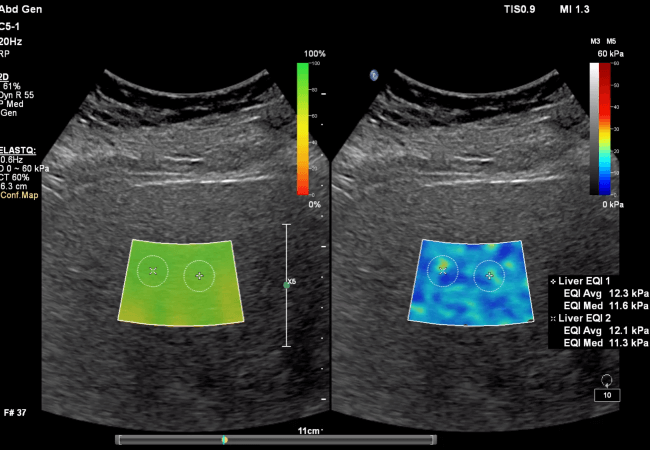

Liver Fat Quantification

Liver fat (visceral fat) is metabolically harmful. This test is performed via ultrasound using FDA-approved software analysis from Philips Healthcare, validated against MRI and liver biopsy to measure liver fat—a key factor in metabolic health and early detection of fatty liver disease.